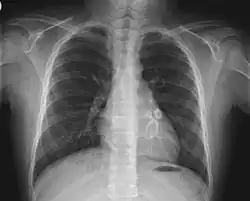

X-ray showing aneurysmal enlargement of the coronary arteries, which is a complication in a Kawasaki syndrome

Symptomatic cases of COVID-19 in children have been relatively uncommon,[30] possibly because they generally experience milder disease.[31] Early infection tends to be associated with mild or no symptoms, while the later pulmonary phase, which can be life-threatening in adults, is usually mild or absent.[32][33] While cases of children with severe symptoms are exceptional, they can occasionally require intensive care.[34][35][36] Fatalities have been rare.[33][37]

In April 2020, a small group of children with evidence of SARS-CoV-2 infection or exposure to COVID-19 were found to display clinical features corresponding to the diagnostic criteria of Kawasaki disease, sometimes accompanied by shock.[34][38] Kawasaki disease is a rare syndrome which mainly affects young children (adult onset has occasionally been reported[39]).[3][40][41] It is a form of vasculitis, where blood vessels become inflamed throughout the body, and it results in a persistent fever.[3] Recovery typically occurs spontaneously, though some children later develop mid-sized or giant coronary artery aneurysms in the heart – a potentially fatal complication.[3][42] Symptoms of toxic shock (a syndrome caused by bacterial toxins) occasionally occur – an association sometimes referred to as 'Kawasaki shock syndrome',[43] which is characterized by systolic hypotension or signs of poor perfusion.[3][44] While the exact cause of Kawasaki disease is unknown, one plausible explanation is that it may stem from an infection triggering an autoimmune and/or autoinflammatory response in children who are genetically predisposed.[45][46] No specific diagnostic test exists for Kawasaki disease, and its recognition is based on various combinations of clinical and laboratory findings (including persistent fever, widespread rashes, enlarged lymph nodes, conjunctivitis, changes to the mucous membranes, and swollen hands and feet).[3][40][47]